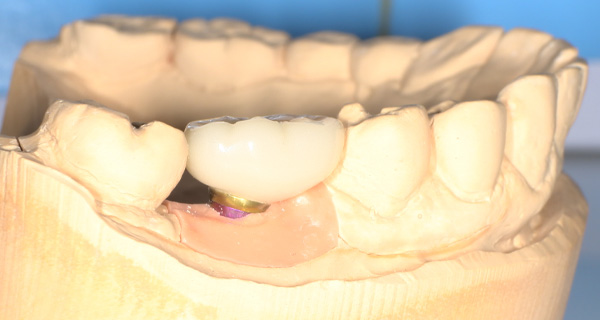

インプラント手術を行いました。

手術の時に使用するサージカルステント

インプラント手術から3ヵ月後、型どりをして、仮歯を製作しました。

仮歯の調整期間を経て、セラミックの歯が入りました。